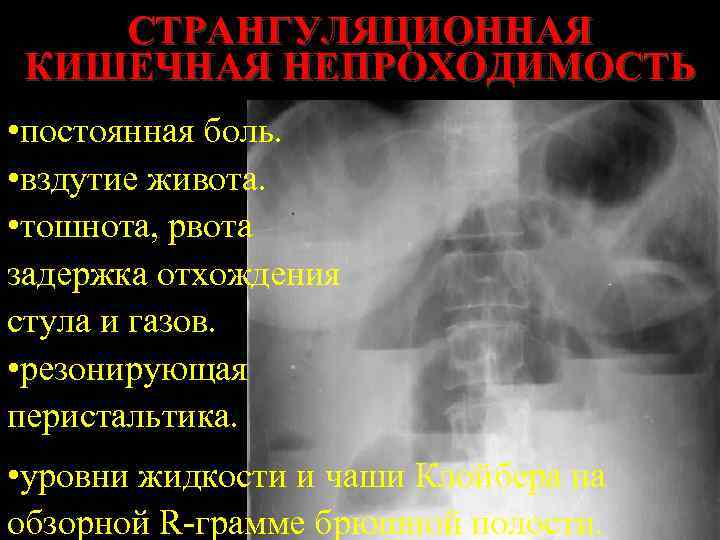

СТРАНГУЛЯЦИОННАЯ КИШЕЧНАЯ НЕПРОХОДИМОСТЬ • постоянная боль. • вздутие живота. • тошнота, рвота задержка отхождения стула и газов. • резонирующая перистальтика. • уровни жидкости и чаши Клойбера на обзорной R-грамме брюшной полости.